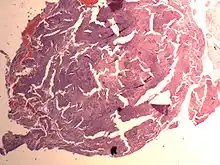

An endometrial stromal nodule is a noninfiltrative, circumscribed proliferation of endometrial stromal cells and is a benign subtype of endometrial stromal tumor. The appearance of the cells is identical to normal endometrial stromal cells. This can only be differentiated from low-grade endometrial stromal sarcoma by confirming lack of infiltration.

The differential includes cellular leiomyoma. Diagnosis may be aided by immunostaining; endometrial stromal nodules are positive for CD10; leiomyomas are positive for caldesmon and desmin (and sometimes CD10).